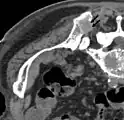

Scanner d'une métastase ostéocondensante dans l'os du crâne d'un patient souffrant d'un carcinome de la prostate. On reconnaît clairement l'extension de la métastase au-delà des limites initiales de l’os.

Par comparaison, scanner de métastases ostéolytiques dans l'os du crâne d'une patiente souffrant d'un cancer du sein. On distingue une ostéolyse plus grande sur le front, et plusieurs plus petites.